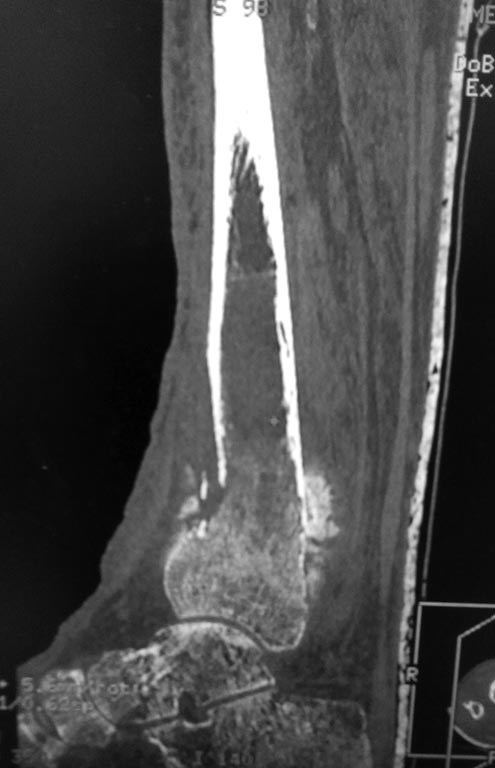

Перелом костей голени в нижней трети

Добрый день!Обратилась женщина 1958 г.р.Травма 08.09.16. Почувствовала боль в правой голени во время сна.

Лечилась амбулаторно с Ds: закрытый перелом костей правой голени в нижней трети без смещения. Повторную травму исключает. На контрольных Rg выявлено смещение отломков, признаки консолидации.

в анамнезе сахарный диабет I типа в течении 29 лет. лабильное течение. Диабетическая нефропатия. ХБП V ст. ХПН терминальная стадия. Хронический програмный гемодиализ. Ренальная остеодистрофия. Принимает лантус 6 Ед *1 раз в сутки. уровень сахара крови 12-15 ммоль\литр. Креатинин 543 мкмоль\литр, ЩФ 1270 Е\л.

А Вы то какой диагноз ставите? От чего сломалось? Ренальная остеодистрофия на фоне ХПН с гемодиализом? Диабетическая остеоартропатия? Пишете, что повторную травму исключает. Но и первичной не было. Последняя рентгенограмма (где перелом без смещения) когда была сделана? Сразу после обнаружения перелома? Там уже есть признаки консолидации. Есть ли признаки периферической нейропатии? Если не вдаваться в подробности, то можно думать об остеосинтезе двойного перелома наружной лодыжки (вероятно, уже срослась). И интрамедуллярном остеосинтезе большеберцовой кости.